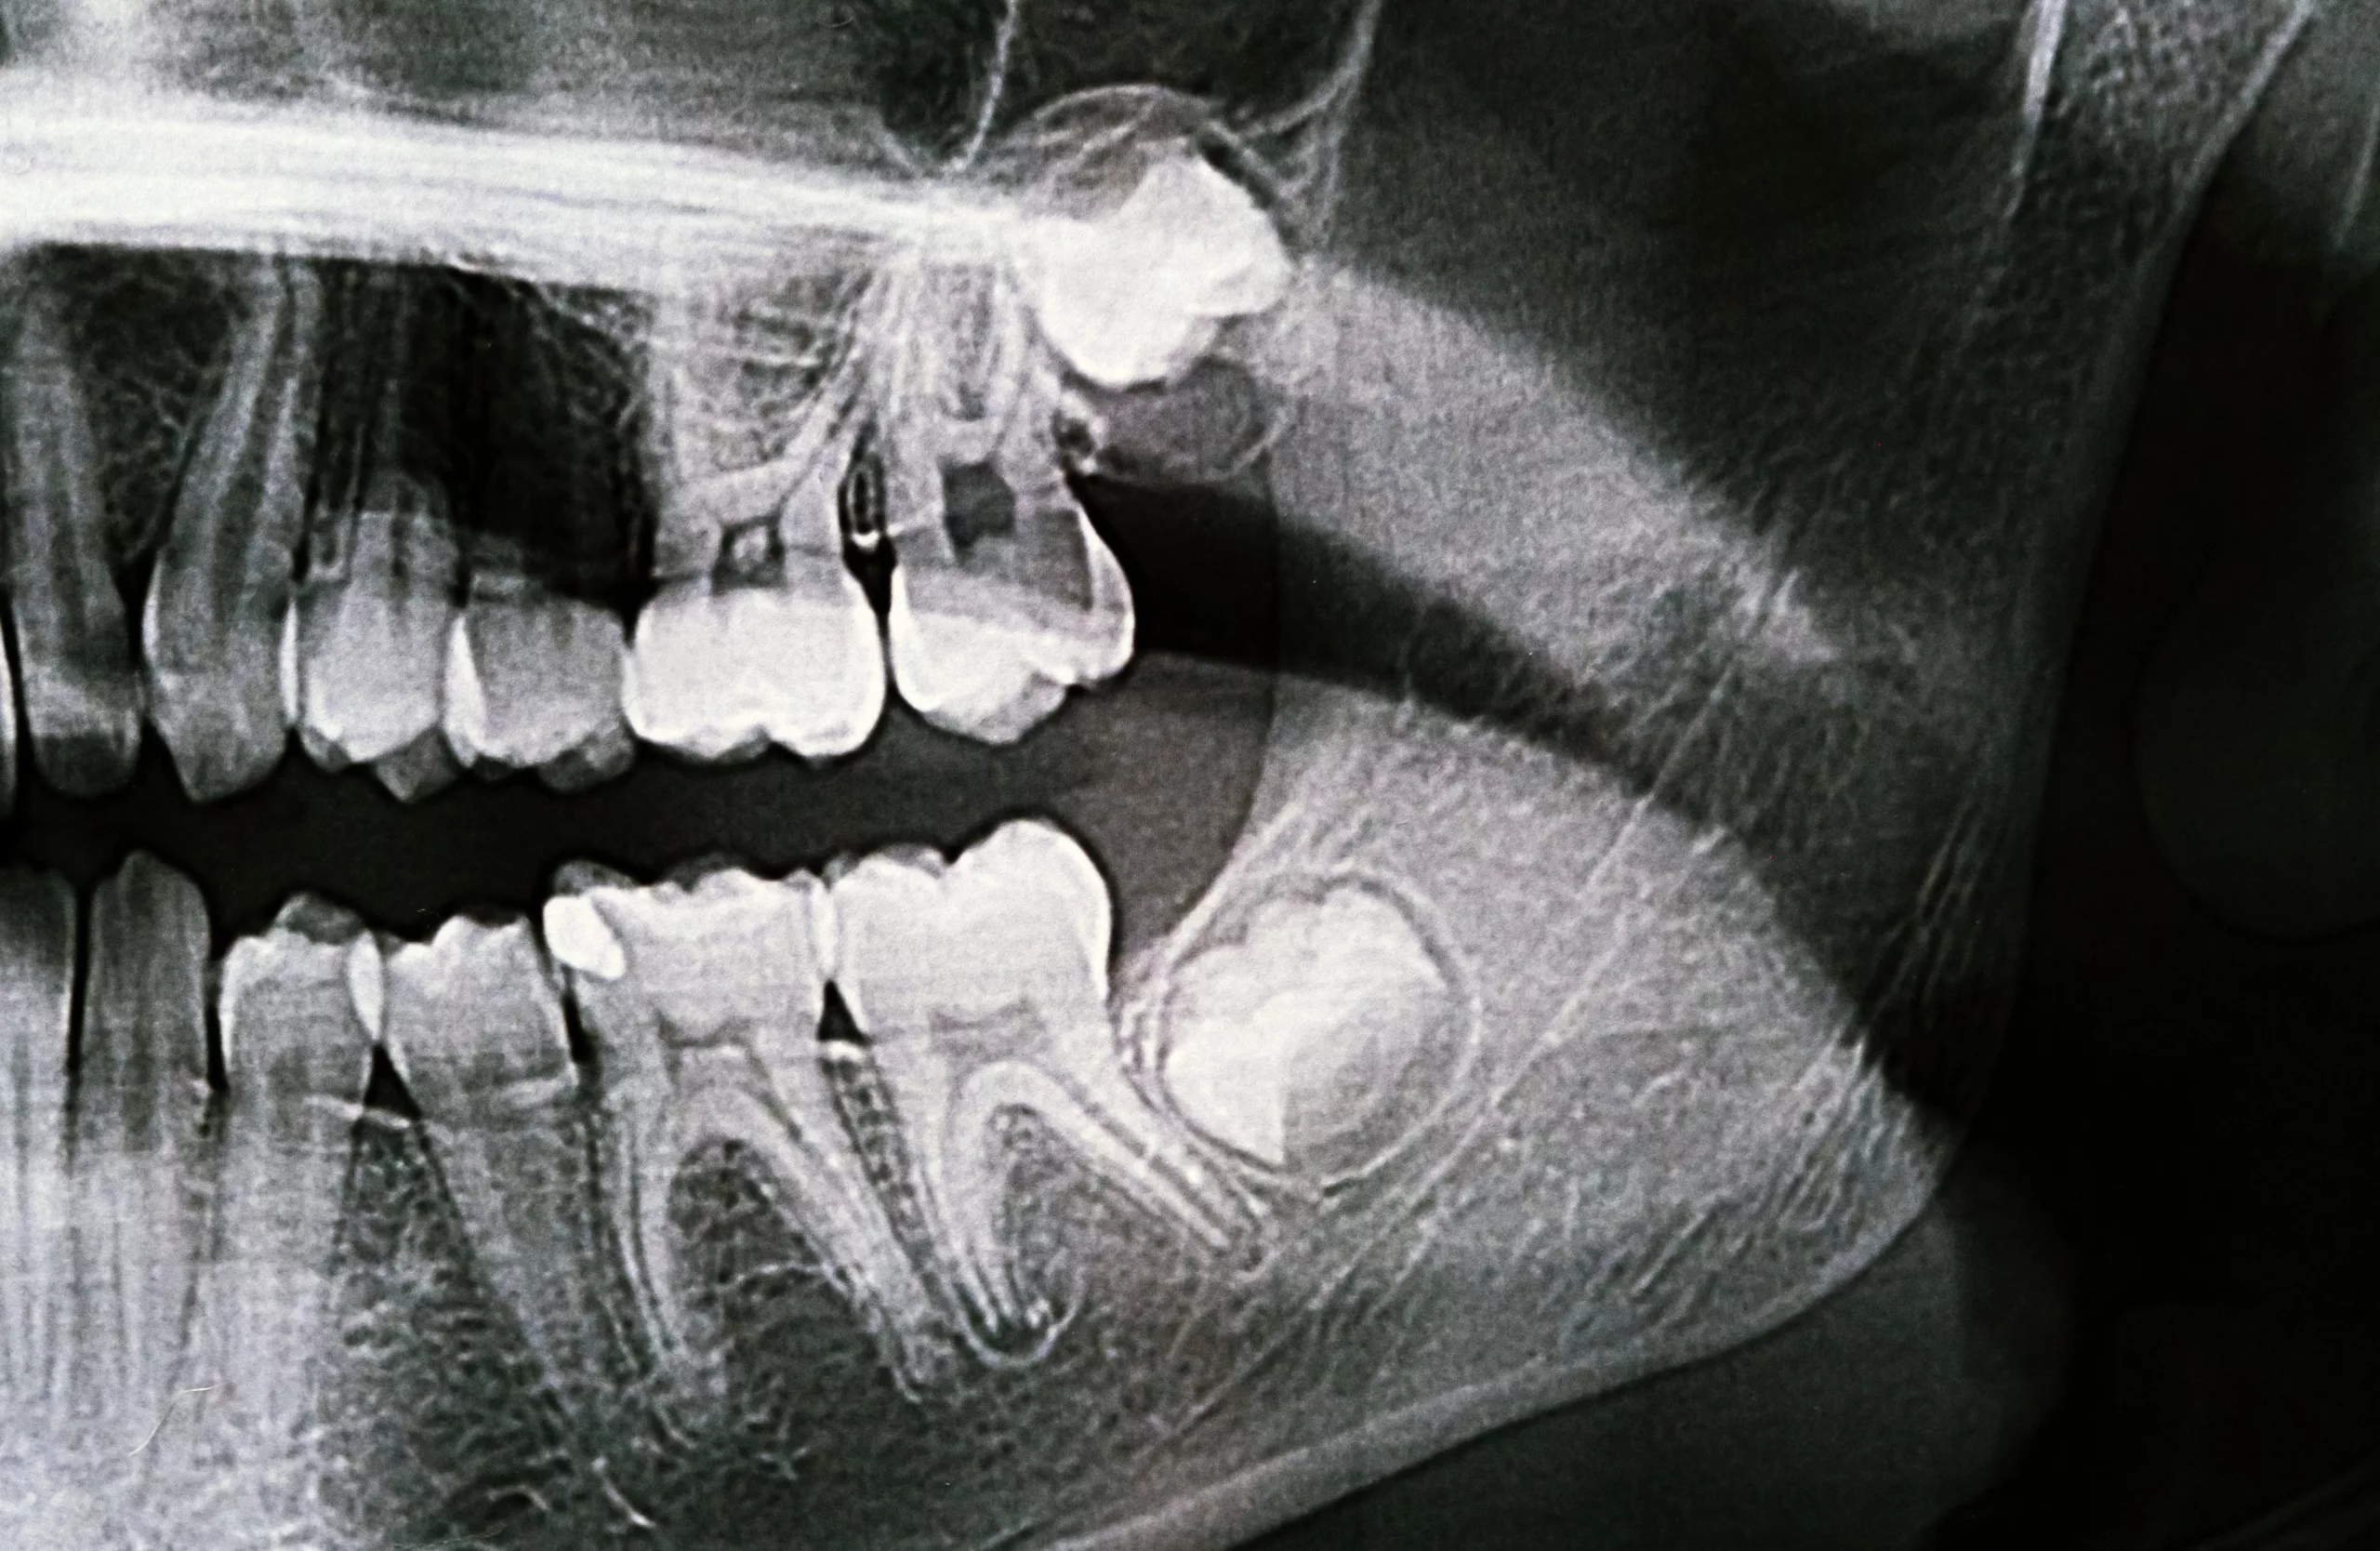

Wisdom tooth removal does not need to feel overwhelming. We focus on explaining what’s happening, why removal may be recommended, and what to expect at each step. Every treatment plan is based on your symptoms, X-rays, and long-term oral health, not a one-size-fits-all approach. Our goal is to keep you comfortable throughout every step of the process, from your initial evaluation to post-extraction care.

After a comprehensive exam and X-rays confirm the need for removal, we’ll develop a personalized treatment plan. The extraction process typically begins with administering a local anesthetic or sedation—depending on your comfort level and the complexity of the case. Once the area is fully numb, your dentist may: